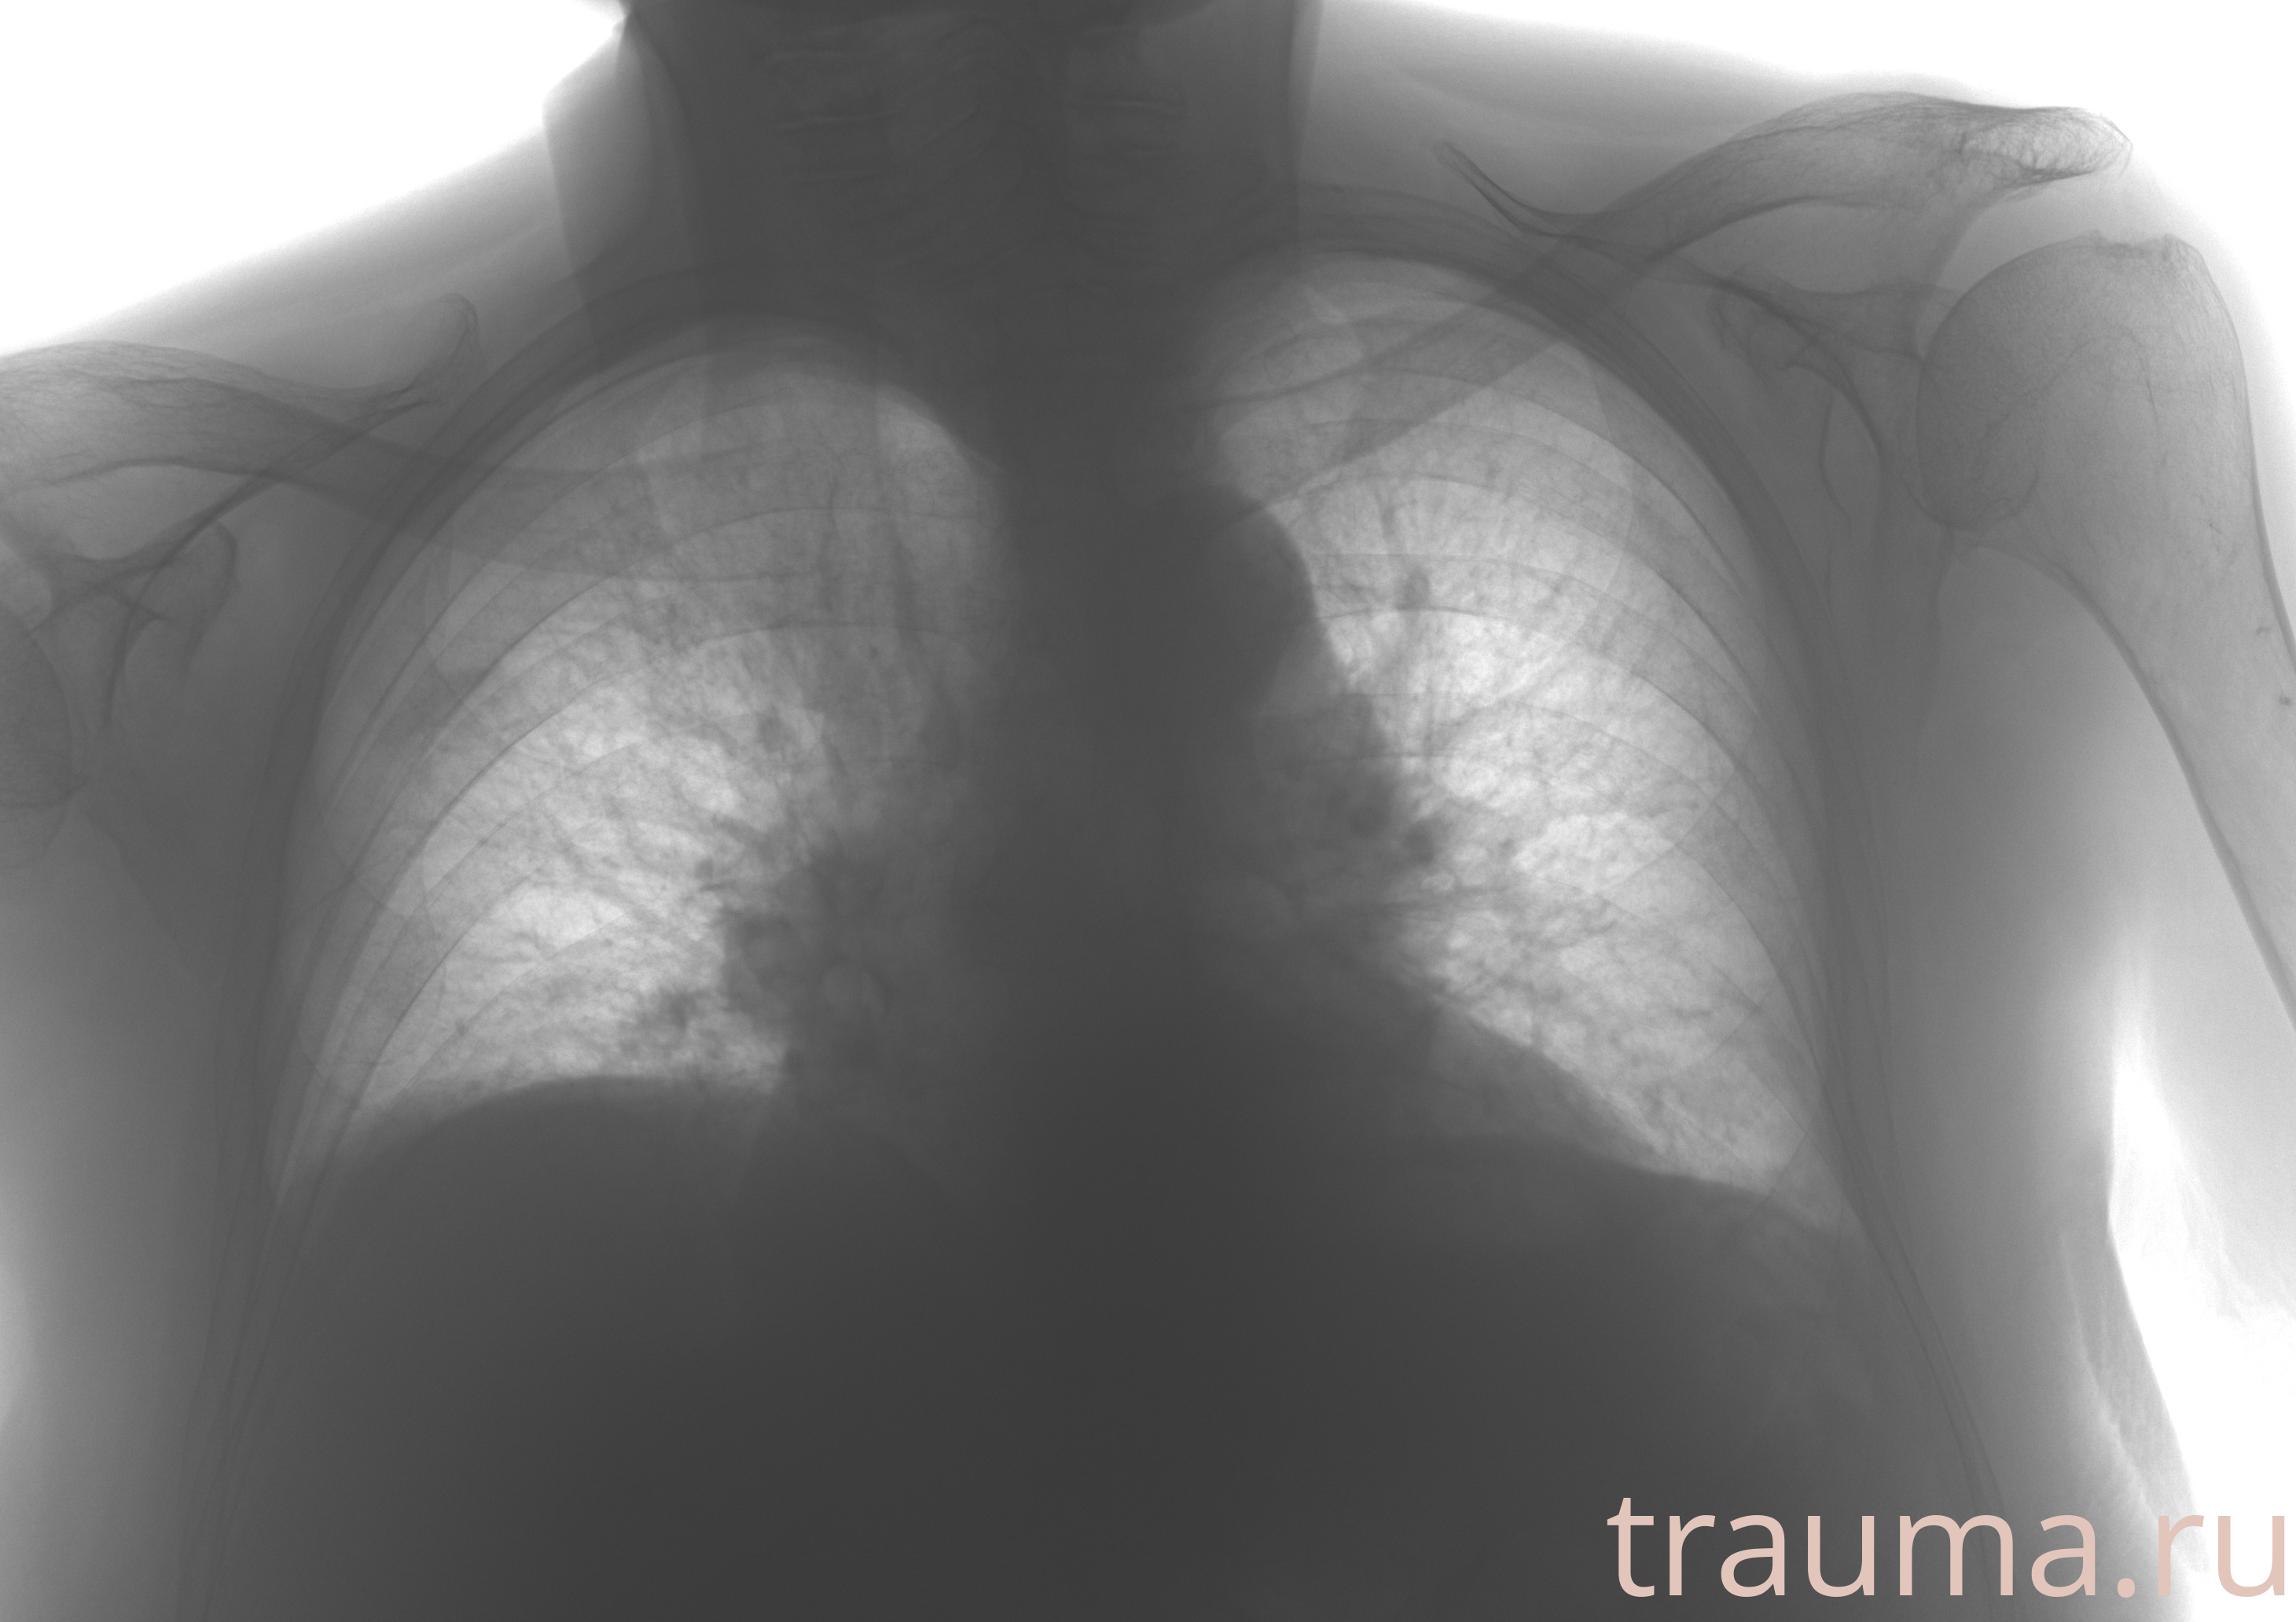

Рентгенограммы

Рентген на дому: по вашему адресу приезжает врач-рентгенолог, травматолог-ортопед с мобильным рентгеновским аппаратом, проводит диагностику травмы или заболевания, делает необходимые рентгенограммы, дает рекомендации по дальнейшему лечению. Получить качественные снимки в домашних условиях возможно благодаря уникальной методике, разработанной МосРентген Центром для института  Склифосовского

Яркость: 1   Контраст: 1   Инвертировать: 0 Увеличение: 1

Перетаскивайте мышь вверх/вниз для контраста, влево/право для яркости. Прокрутка колесом изменяет масштаб. Нажмите Сбросить для возврата к исходному изображению. При увеличении держите мышь в той области, которую хотите рассмотреть.